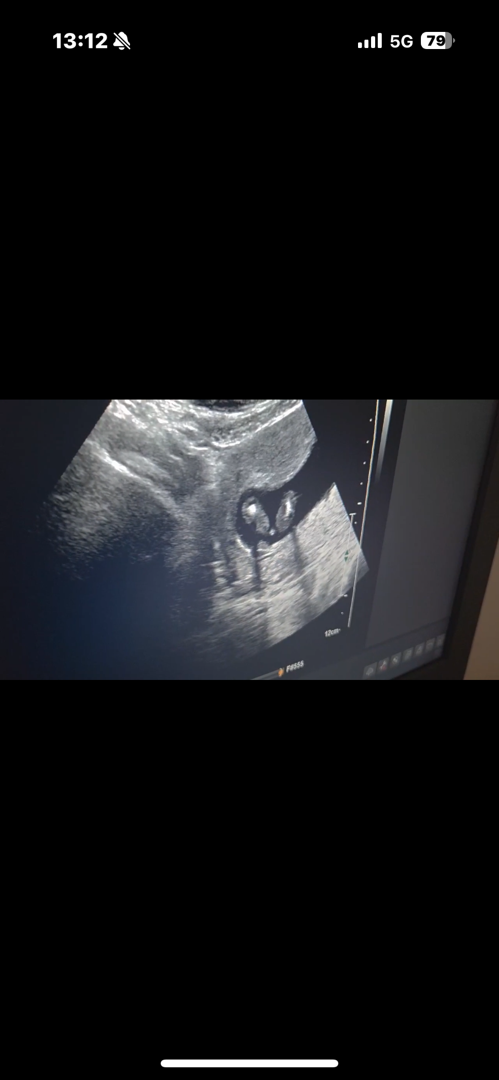

14주 4일인데,,, 성별혹시 봐주실수있을까요?

다리사이인거죠? 14주차이신데 삼각점안보여서 딸인것 같아요 아들은 엄청 확실하게 보여요!

성별알려주실수맀을까요,,,?